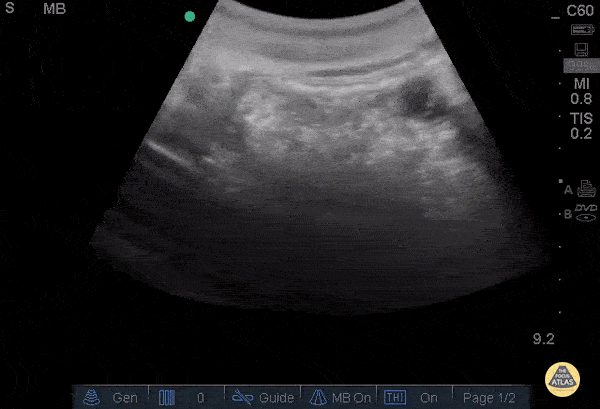

Bowel-GI - Enlarged pylorus with gastric outlet obstruction

28 y/o F no significant PMH with 1 month epigastric abdominal pain associated with daily emesis in the mornings and postprandial discomfort.. Patient notes she feels a firmness in her epigastrium. POCUS with an enlarged pylorus with gastric outlet obstruction, confirmed with formal sono. Admitted and evaluated with EGD by GI, found to have peptic ulcer in the antrum with edema and degree of gastric outlet obstruction. Dr. Adrian Aurrecoechea, Dr. Andrew Aherne - Kings County Hospital